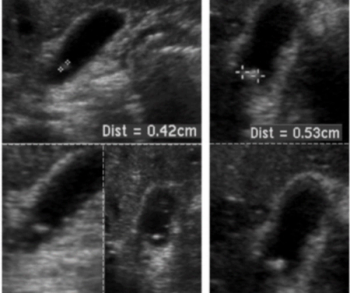

For DBT breast cancer screening, 47 percent of radiologist-only flagged false positives involved mass presentations whereas 40 percent of AI-only flagged false positive cases involved benign calcifications, according to research presented at the recent American Roentgen Ray Society (ARRS) conference.